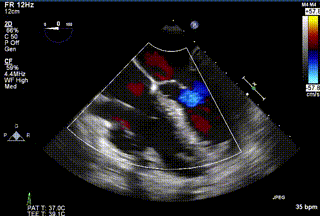

2021年12月24日,復(fù)旦大學(xué)附屬中山醫(yī)院葛均波院士團(tuán)隊(duì)成功應(yīng)用LuX-Valve Plus為一例極重度三尖瓣反流(TR)合并房顫、房缺的患者完成了經(jīng)血管三尖瓣置換術(shù),這是在前基礎(chǔ)上,本周完成的第三例經(jīng)血管三尖瓣置換手術(shù),葛均波院士、周達(dá)新教授等與心外科魏來教授、賴顥教授,心超室的潘翠珍教授、李偉教授及麻醉科的郭克芳教授共同完成了本周手術(shù),均獲得圓滿成功!患者術(shù)后超聲顯示無TR,臨床癥狀明顯改善。本周手術(shù)的成功也為LuX-Valve Plus救治性臨床研究添上了濃墨重彩的一筆。

三例患者入院后,葛均波院士團(tuán)隊(duì)周達(dá)新教授、潘文志教授、張?jiān)床┦俊㈥惿┦考靶某业呐舜湔浣淌?、李偉教?/strong>對(duì)患者的情況進(jìn)行詳細(xì)評(píng)估和討論,最終決定為三例患者選擇LuX-Valve Plus40mm、50mm和50mm型號(hào)的瓣膜進(jìn)行手術(shù)治療。手術(shù)后即刻拔除氣管插管,術(shù)后患者三尖瓣反流癥狀得到顯著改善,復(fù)查心超結(jié)果顯示人工三尖瓣瓣膜支架固定穩(wěn)定,瓣葉關(guān)閉形態(tài)未見異常,未見明顯反流。